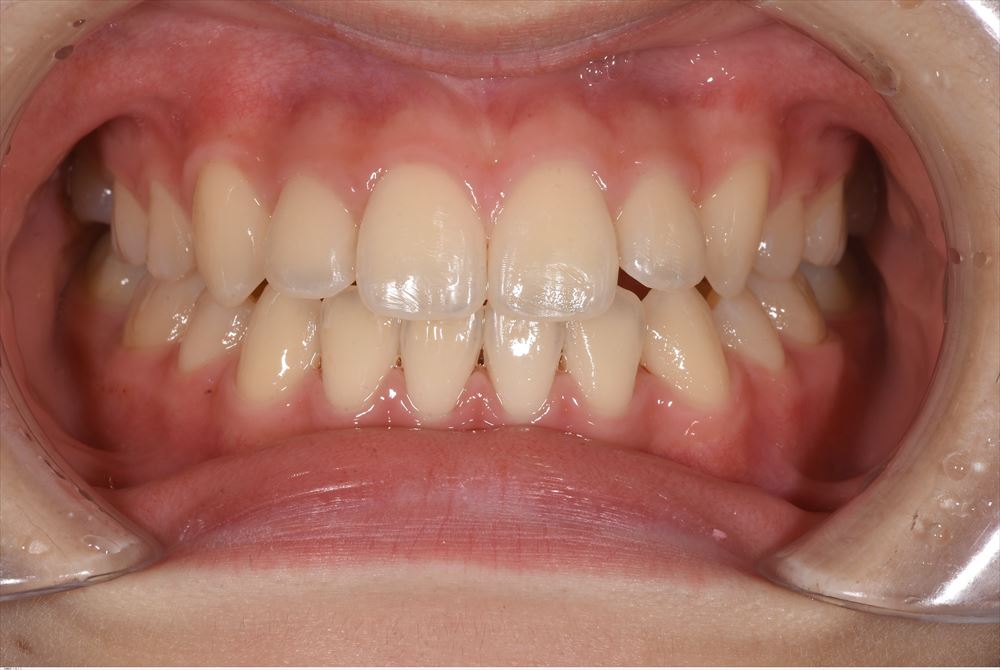

今日は矯正の装置を外した女の子。外してとても喜んで頂けました。

術前。あらま。

今日

リテーナー使ってねー。